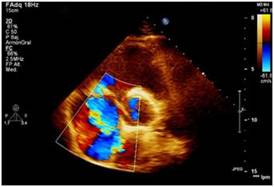

Figura 2: Ecocardiograma transtorácico. Plano paraesternal, eje corto o transversal a nivel de los grandes vasos. Doppler color que muestra jet de regurgitación tricuspídea severa por déficit en la coaptación valvular tricuspídea.

En el examen físico se detectaron los siguientes datos positivos: peso: 83 kg, talla: 1,76 m y un índice de masa corporal de 26.79 kg/m2. Temperatura axilar de 39.2 ◦C. En la región del cuello se observó una distensión venosa yugular con una onda sistólica prominente. En el sistema cardiovascular se ausculta un soplo sistólico iii/vi de mayor intensidad en el 4.◦ espacio intercostal paraesternal izquierdo y la región subxifoidea, con un aumento de intensidad durante la inspiración, una presión arterial de 110/80 mmHg y una frecuencia cardíaca de 97 latidos por minuto. En el abdomen se advirtió la presencia de una hepatomegalia de alrededor 1 cm por debajo del reborde costal, de consistencia firme, no dolorosa. Tejido celular subcutáneo infiltrado en ambos miembros inferiores hasta 1/3 inferior tibial de fácil godet. Como parte de los análisis de laboratorio realizados, se reportó una leucocitosis ligera con desviación a la izquierda. Velocidad de eritrosedimentación de 96 mm/h. PCR, positiva. Factor reumatoideo, positivo. Serología VIH, negativa. Se realizó un ecocardiograma transtorácico (ETT) (figs. 1 y 2), donde se apreció una imagen ecogénica en la valva anterior de la tricúspide, compatible con vegetación mayor de 17 × 21 mm que generaba déficit en la coaptación valvular con insuficiencia de la misma, además de una disfunción sistólica del ventrículo derecho con un TAPSE de 8 mm y un ventrículo derecho de 41 mm en su base, con des- plazamiento del tabique interventricular hacia la izquierda. Aurícula derecha dilatada, con desplazamiento del septum interauricular hacia la izquierda. Flujo pulmonar con un tiempo de aceleración de 95 ms y una presión media de la arteria pulmonar de 32 mmHg. Se confirmaron hallazgos a través de ecocardiograma transesofágico (ETE), realizado sin complicaciones.